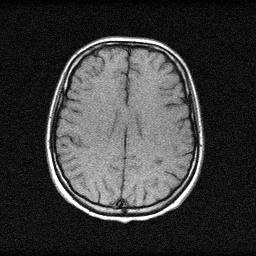

Method: CPU_baseline | Mismatch: nominal (nominal=True, perturbed=False)

Ground Truth